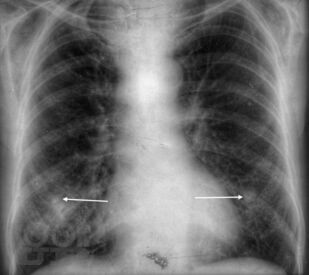

Рентгеноанатомия органов грудной клетки

В данном электронном пособии систематизированы и подробно изложены сведения о рентгеновской анатомии органов грудной клетки.